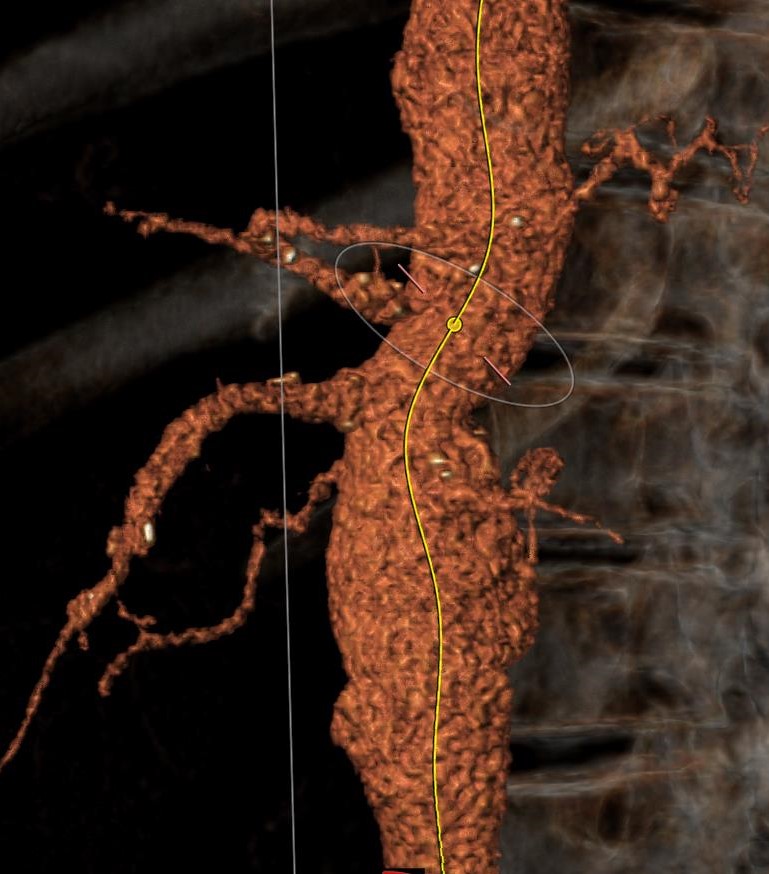

Περίπτωση 3

Άνδρας ασθενής 65 ετών με ανεύρυσμα κοιλιακής αορτής μέγιστης διαμέτρου 5,8 εκατοστών που αρχίζει αμέσως κάτω από τις νεφρικές αρτηρίες (παρανεφρικό), παχύσαρκος, με πολλαπλές συνοδές παθήσεις που αποκλείουν την ανοιχτή χειρουργική αποκατάσταση, η οποία με την σειρά της παρουσιάζει σημαντική πιθανότητα για μετεγχειρητικές επιπλοκές

Αντιμετωπίστηκε ενδαγγειακά με την τεχνική χρησιμοποίησης εξατομικευμένου μοσχεύματος τύπου Zenith με πλάγιες οπές (fenestrations), στις 2 νεφρικές αρτηρίες και την άνω μεσεντέριο αρτηρία με επιπρόσθετη ευρεία εγκοπή (scallop) για την κοιλιακή αρτηρία, το οποίο σχεδιάστηκε αποκλειστικά για την περίπτωση του